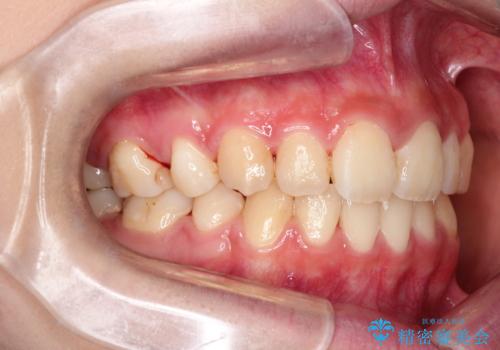

【ハーフリンガル】口元を下げたい!

- ハーフリンガル

- 口元が出ていることを主訴に来院されました。

歯を抜いてスペースを作ることで、前歯を下げることができました。

ハーフリンガルということで治療期間が3年近くかかりましたが、口元もしっかり下がり満足していただきました。